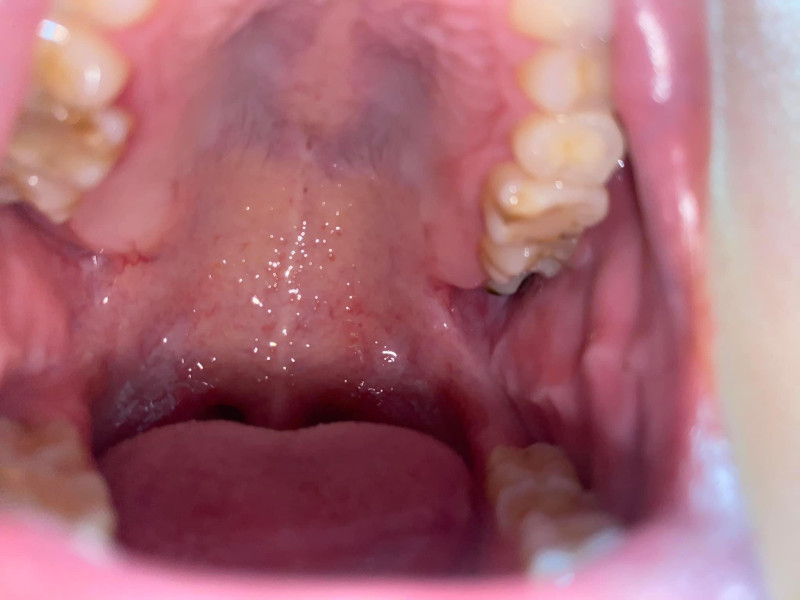

Chào bạn trường hợp răng 8 mọc lên sâu hoặc ko sâu cũng sẽ gây ra 1 số biến chứng . Bạn nên nhổ càng sớm càng tốt để ko ảnh hưởng đến quá trình sinh hoạt và sức khoẻ của bạn nhá. Chúc bạn thành công

Chào bạn trường hợp răng 8 mọc lên sâu hoặc ko sâu cũng sẽ gây ra 1 số biến chứng . Bạn nên nhổ càng sớm càng tốt để ko ảnh hưởng đến quá trình sinh hoạt và sức... Xem thêm